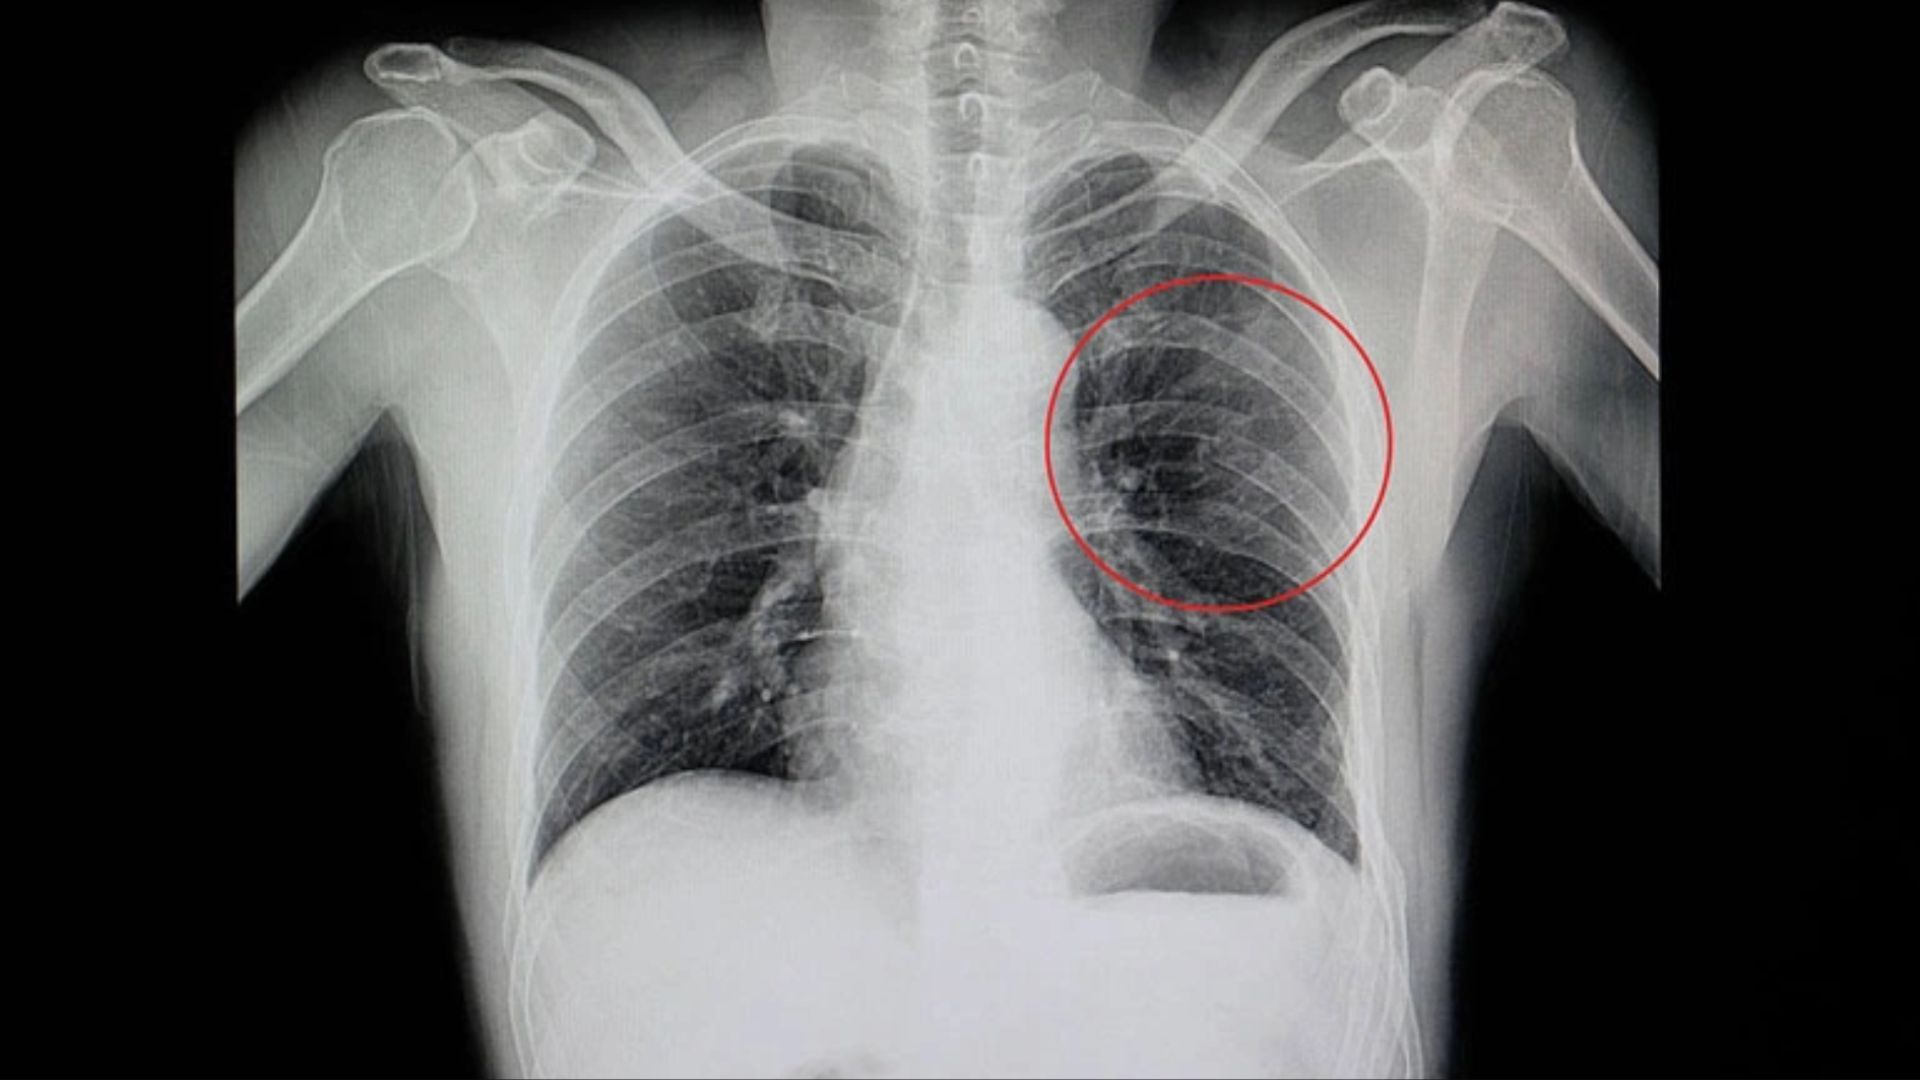

- X-quang ngực: Phương pháp đầu tay, giúp phát hiện vị trí và số lượng xương gãy cũng như loại trừ tràn khí màng phổi. Hình ảnh cho thấy đường gãy ngang hoặc xoắn ốc trên xương sườn.